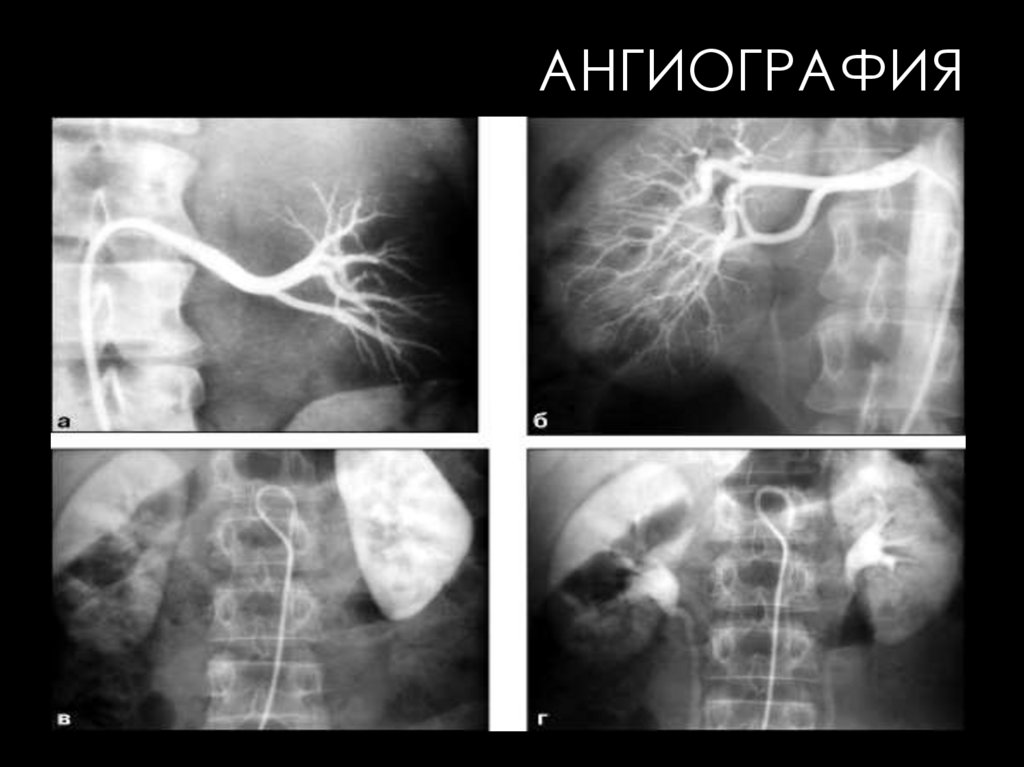

АНГИОГРАФИЯ

ПОЧЕЧНАЯ АНГИОГРАФИЯ

На серийных снимках последовательно отображаются 4

фазы прохождения РКС в почках и его экскреция в

чашечно-лоханочный комплекс.

I фаза - ранняя артериальная. Хорошо выявляются

магистральные почечные артерии и их ветви.

II фаза - поздняя артериальная с контрастированием

мелких разветвлений внутрипочечных артерий.

76.

(ПРОДОЛЖЕНИЕ)

• III фаза - нефрографическая. В этой фазе

изображение

почечных

сосудов

отсутствует, но

отмечается значительное повышение интенсивности

тени паренхимы почки, обусловленное скоплением РКС

в капиллярах и почечных канальцах.

• IV фаза - урографическая, наступающая тогда, когда

контрастное вещество начинает выделяться с мочой и

появляется

чашечно-лоха-ночного

комплекса